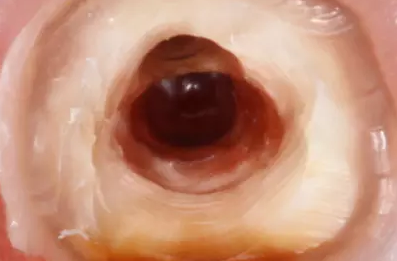

清理髓腔后,用中倍和高倍仔細(xì)查看穿孔的位置大小形狀和軟組織狀況。然后用小棉球?qū)⒏浇母芸诙氯?,以免異物掉入根管?nèi)。徹底清洗穿孔后,將調(diào)拌好的MTA材料充填到穿孔處,稍稍加壓,反復(fù)充填直到將穿孔填滿,使用小蒸餾水濕棉球整形,完成充填后,清理掉多余的材料,檢查外形。

根尖區(qū)和根管中下l/3穿孔,在鏡下可用MTA根充根尖區(qū)并同時(shí)堵塞穿孔部位。根管中上部穿孔,可進(jìn)行根尖部的垂直加壓法根充.穿孔部位MTA修補(bǔ),或穿孔部位以下及穿孔區(qū)全部用MTA充填和修補(bǔ)。

對(duì)于根管口周圍或髓底穿孔,鏡下視野清楚,可于穿孔部位直接用MTA修補(bǔ),并于表面置濕棉球,一周后根管充填。免費(fèi)口腔招聘整理對(duì)于大的穿孔,為防止MTA超出穿孔處,可首先在穿孔區(qū)填入可吸收膠原,在壓入MTA材料封閉穿孔區(qū)。